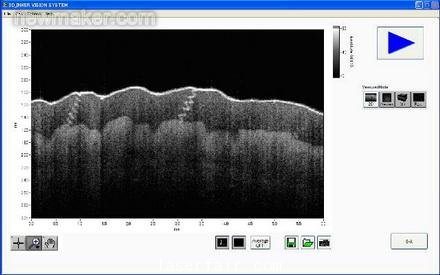

我們的系統(tǒng)現(xiàn)在可以更快地顯示物體(包括人體器官和其他移動的樣品)的圖像。而且,新的基于FPGA的系統(tǒng)可以提供實時測量信號處理,通過消除測量和顯示之間的延遲,提高顯示性能。圖4表示成像系統(tǒng)的LabVIEW面板。

newmaker.com

圖4. SS- OCT成像系統(tǒng)的面板